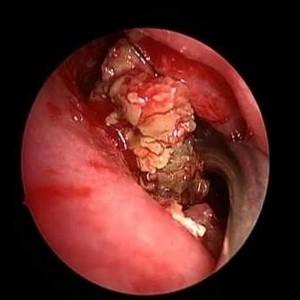

Хирургическое вмешательство

Если медикаментозное лечение не приносит результатов, врач может рекомендовать прокол носовой пазухи.

Во время процедуры выполняется пункция с использованием специальной иглы, после чего с помощью медицинского шприца осуществляется очистка гайморовой полости.

Затем следует промыть нос антибактериальными растворами и пройти курс противогрибковых препаратов.

| Эндоскопическая синусотомия | Удаление грибковых масс, пораженных тканей и восстановление дренажа пазух с помощью эндоскопа. | Основной метод лечения при инвазивных и неинвазивных формах. Позволяет максимально сохранить здоровые ткани. |